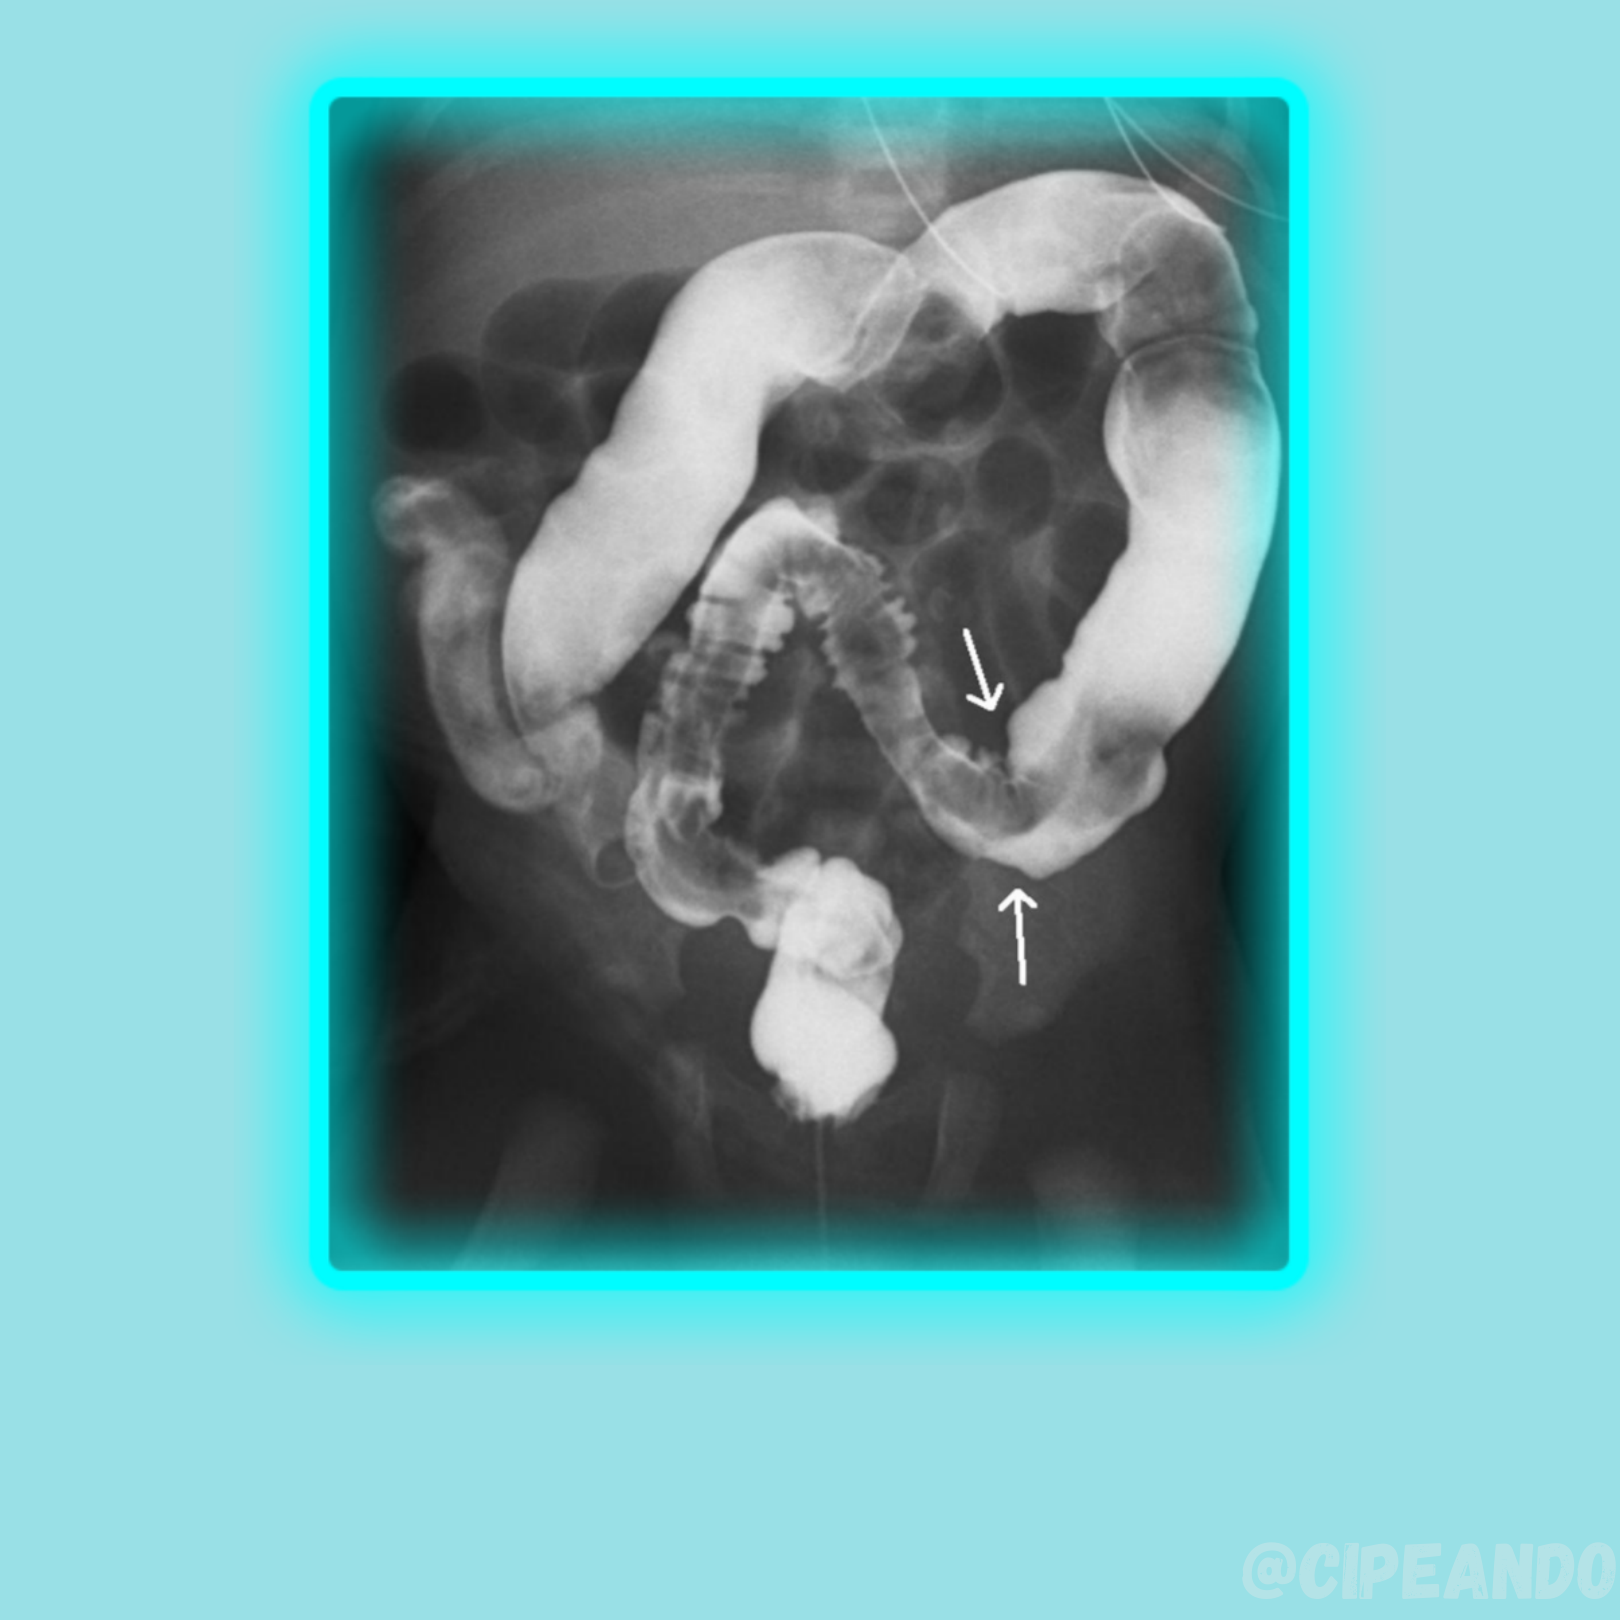

Caso de Radiologia - Paciente com Constipação Crônica : r/medicine

DICAS DE RADIOLOGIA - Tudo Sobre Radiologia: DOENÇAS DO INTESTINO - MEGACÓLON CONGÊNITO E ADQUIRIDO